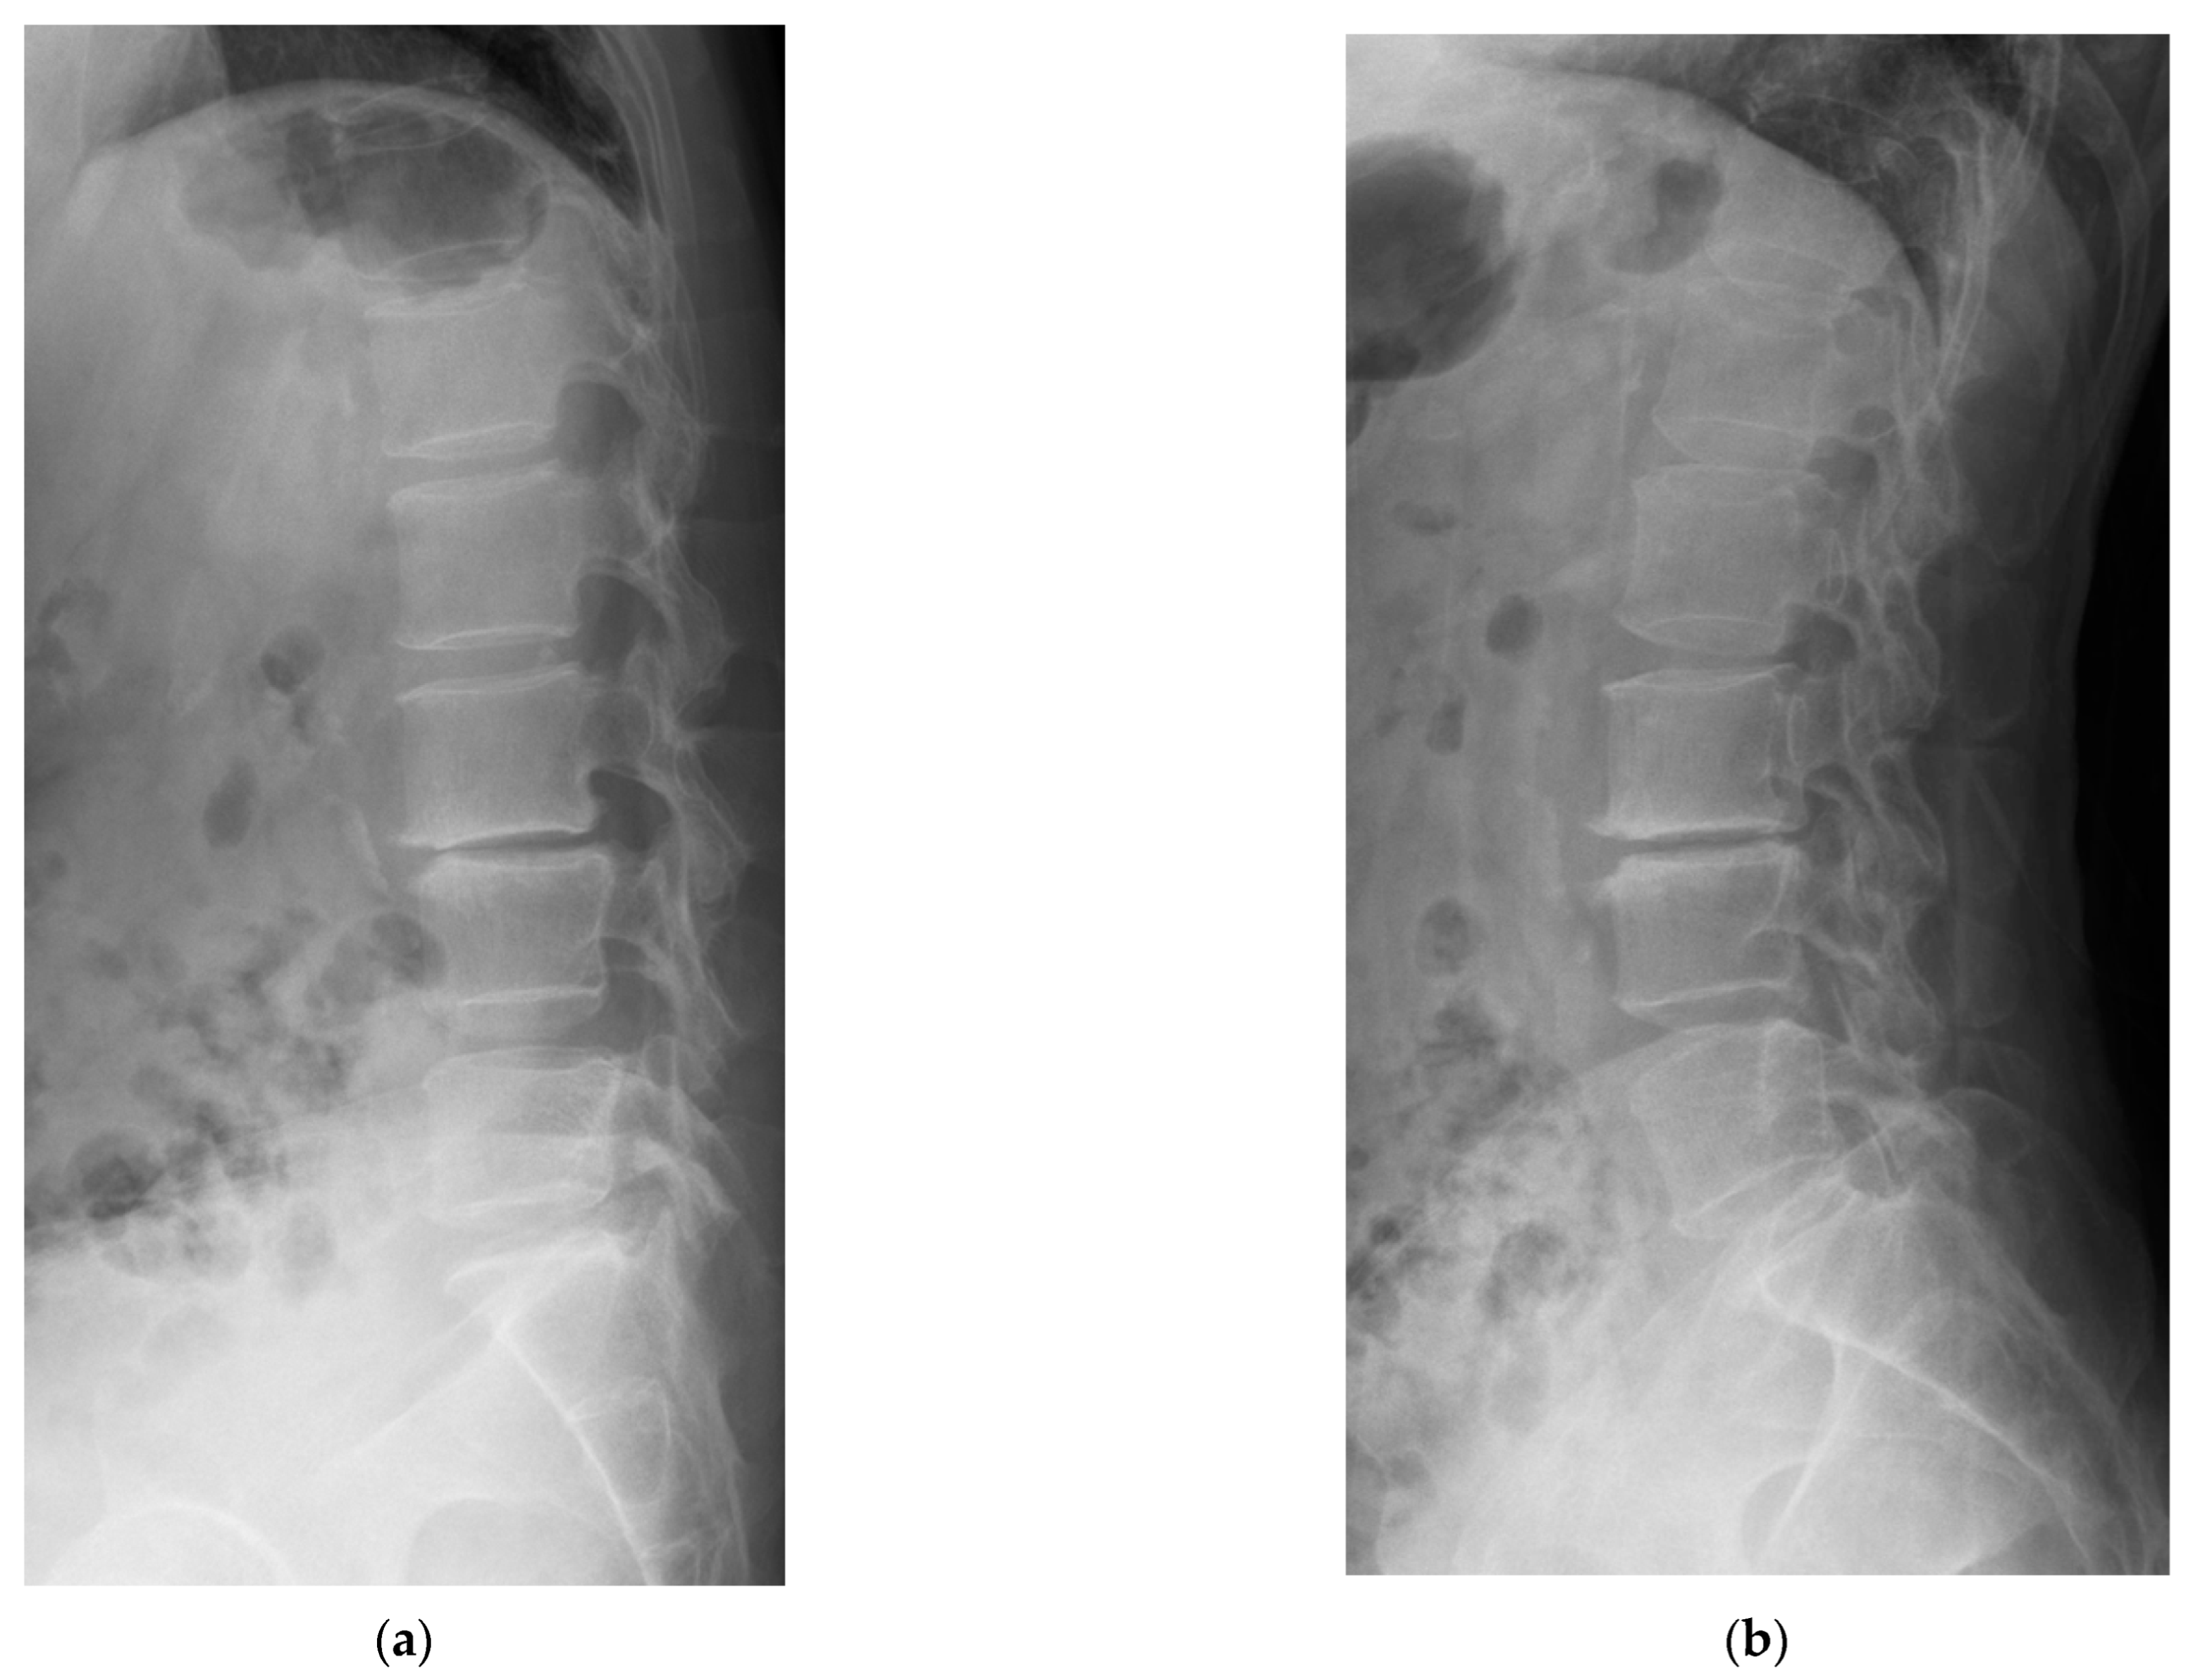

4.1. Case 1: Madam M

4.2. Case 2: Madam R

4.3. Case 3: Madam M